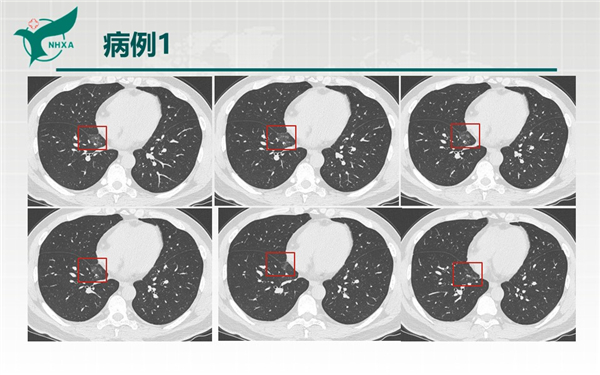

【病例分享】新型冠狀病毒肺炎3例(西安市第九醫(yī)院)

幻燈片6.jpg